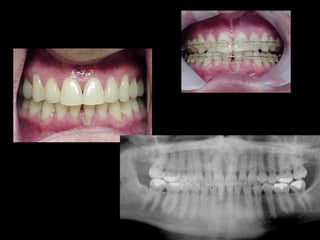

Antes (arriba) Después (derecha)

La paciente muestra una franca disgnatia, clínicamente

observamos malposición dentaria secundaria a la falta de

armonía máxilomandibular.

Marcada Clase III

Hábito Lingual

Sobremordida horizontal: –1.5 mm

Sobremordida vertical: + 1 mm.

La paciente muestrauna franca disgnatia, clínicamente observamos malposición dentaria secundaria a la falta de armonía máxilomandibular. La paciente muestra una franca disgnatia, clínicamente observamos malposición dentaria secundaria a la falta de armonía máxilomandibular.

Marcada Clase III HábitoLingual Marcada Clase III Hábito Lingual Sobremordida horizontal: –1.5 mm Sobremordida vertical: + 1 mm. Sobremordida horizontal: –1.5 mm Sobremordida vertical: + 1 mm.